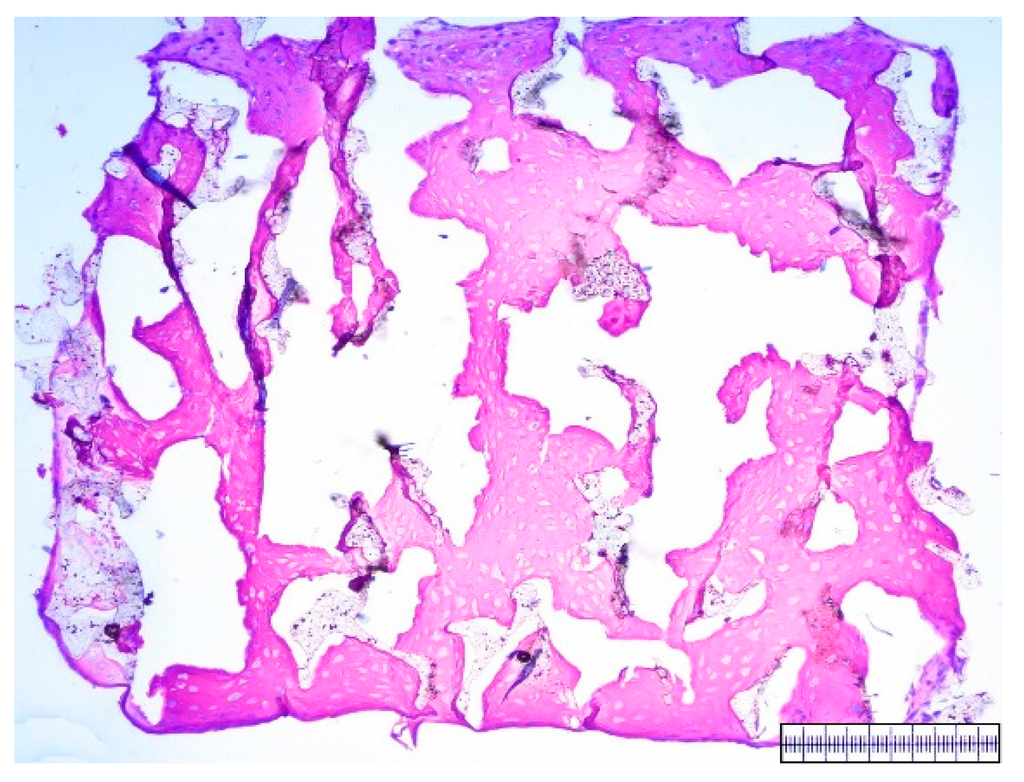

3.3. In Vitro Chondrogenesis